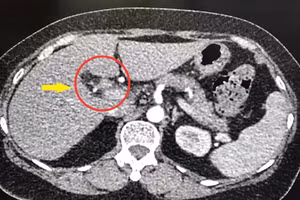

GD&TĐ - Bệnh viện Chợ Rẫy (thành phố Hồ Chí Minh) vừa phẫu thuật tách khối u đầu tụy nặng 2,2kg cho một bệnh nhân nữ nghĩ cơ thể mập lên tuy nhiên đi khám mới phát hiện mắc khối u lớn.